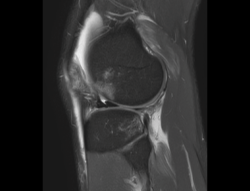

4.3. Osteocondritis

En la osteocondritis se aprecia una lesión subcondral caracterizada por resorción ósea, colapso y la formación de un secuestro.

El estudio por RM es una herramienta valiosa para diagnosticar e identificar las lesiones del cartílago. Conocer el aspecto del cartílago y saber cuánto y cuándo se lesiona, basándose en las clasificaciones actuales, permiten al radiólogo proporcionar la máxima información al clínico(20).

Figura 53. Corte de secuencia sagital (A) y axial (B) T2 Fat-Sat de RM de rodilla: lesiones osteocondrales en el fémur y la rótula.

Numerosos estudios demuestran la utilidad de la RM para definir la estabilidad o inestabilidad de la lesión en la osteocondritis, destacando su carácter no invasivo y la capacidad de valorar la progresión y la respuesta al tratamiento(21)(Figuras 53 y 54).